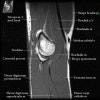

2. Axial section

1) The tendons of the Biceps Brachii and Brachiallis muscles transversely as they insert onto the Radius and Ulna respectively. 2) The distal Triceps tendon is also well evlauated in this plane.